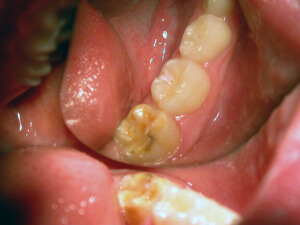

Caries

How caries occurs?

Caries is a disease. It is the most widespread disease in the world. The bacterial dental plaque (also called a biofilm) is the main cause of the infection of the teeth and the supportive tissues, i.e. of the caries and periodontal diseases respectively. The accumulation of dental plaque and the colonization of bacteria lead to the appearance of dental and periodontal pathology.

Microbes cling on various surfaces and form the biofilm. In addition, frequent intake of carbohydrates (especially sweets) gets metabolized to acids. The pH of dental plaque becomes acidic repeatedly, and that favors acid tolerant bacteria, such as streptococci and lactobacilli that are the most dangerous bacteria for caries.

Research shows that caries as a disease is identified at certain groups of people that are more prone to it. 80% of the carious cavities are located on 20% of the world’s population.